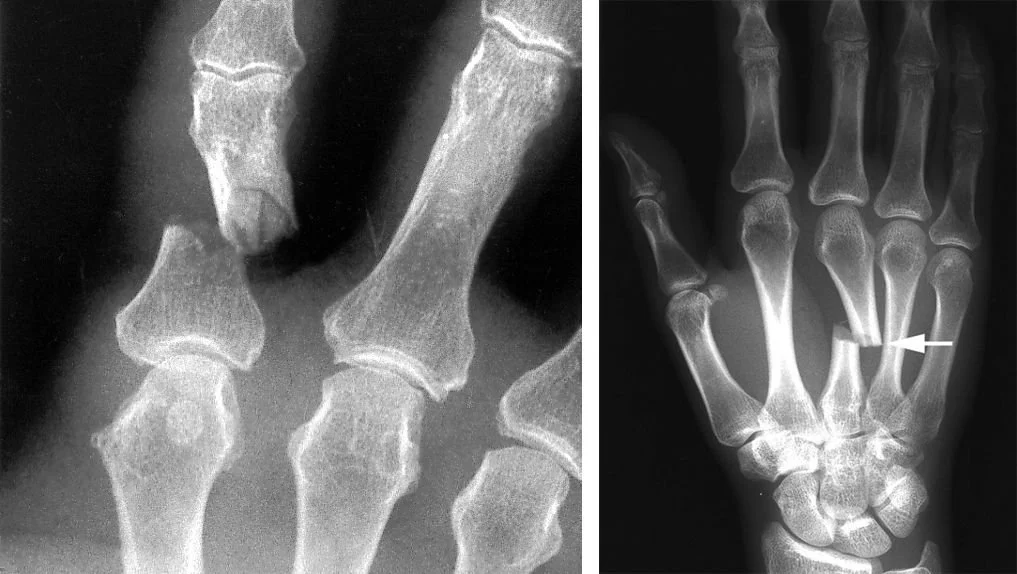

એક ટેસ્ટમાં, તેનો ઉપયોગ કરીને ત્રણ મિનિટથી ઓછા સમયમાં હાડકું જાેડવામાં આવ્યું હતું, જ્યારે પરંપરાગત પદ્ધતિઓમાં મોટો ચીરો કરીને સ્ટીલની પ્લેટ અને સ્ક્રૂ નાખવા પડે છે. જણાવી દઈએ કે, આ ગુંદરનો ઉપયોગ ૧૫૦થી વધુ દર્દીઓ પર સફળતાપૂર્વક કરવામાં આવ્યો છે.

પરીક્ષણોમાં જાણવા મળ્યું હતું કે, આ ગુંદર ૪૦૦ પાઉન્ડથી વધુ વજન સહન કરી શકે છે અને તેની શીયર સ્ટ્રેન્થ ૦.૫ સ્ઁટ્ઠ અને કમ્પ્રેસિવ સ્ટ્રેન્થ ૧૦ સ્ઁટ્ઠ જેટલી છે. આનાથી એવું લાગે છે કે, આ ગુંદર પરંપરાગત પ્લેટ અને સ્ક્રૂનું સ્થાન લઈ શકે છે. આ ઉપરાંત, તે શરીરમાં રિએક્શન કે ચેપનું જાેખમ પણ ઘટાડે છે.